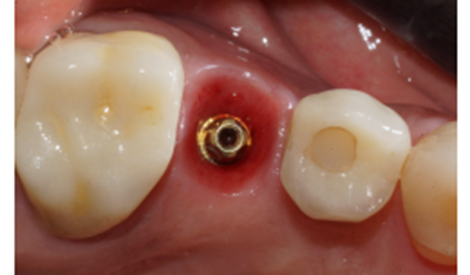

Diante das circunstâncias, foi eleito um pilar Ideale reto de 3.3 X 4.0 X 1.5 mm de transmucoso, que foi instalado a 20 Ncm. O escaneamento desse pilar foi realizado para a confecção de um provisório fresado em PMMA. Após 15 minutos da instalação e do escaneamento do pilar, o provisório fresado foi instalado sobre o pilar Ideale e aparafusado com o parafuso Torx a 10 Ncm. Foi então realizada uma radiografia após a instalação e a paciente foi marcada para retornos de 7 e 15 dias, sendo que após os retornos, a paciente realizou sua viagem (Figuras 11, 12, 13 e 14).